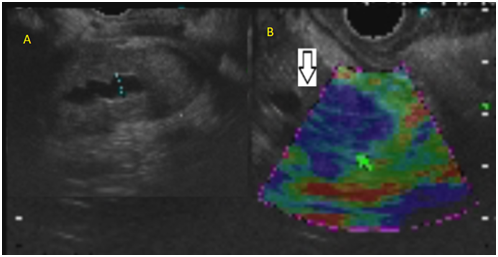

Endosonography showed a heterogeneous and hypoechoic nodular lesion of 15mm in the head of the pancreas. It was poorly delimited and had irregular edges. Ultrasound elastography revealed an indurated lesion and an area where the dilation of the pancreatic duct suddenly narrowed (Figure 3). Fine needle aspiration was performed and findings of the cytological and cell block study indicated an adenocarcinoma. The case was consulted with the surgical team and a pancreatoduodenectomy was performed without incidents. Biopsies demonstrated glandular atrophy and lymphocyte plasmocytic infiltrate (Figure 4). Immunotyping evidenced IgG4 presence in the cytoplasm of plasma cells, with an IgG4/IgG ratio greater than 40% (Figure 5). Finally, a focal autoimmune pancreatitis was diagnosed.

Figure 3 A. dilation of the pancreatic duct suddenly narrows. B. indurated lesion .